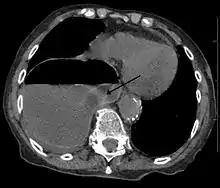

Uma hérnia diafragmática ao lado direito, com o estômago no peito (lado esquerdo da imagem marcado com uma seta). Note o nível de fluido de ar no estômago.

O diagnóstico pode ser feito por tomografia computadorizada ou raio-x. Diagnosis can be made by either CT or Xray.